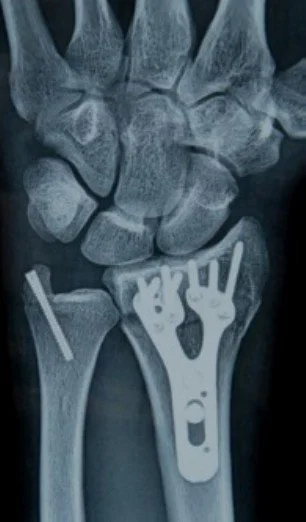

Common Operations